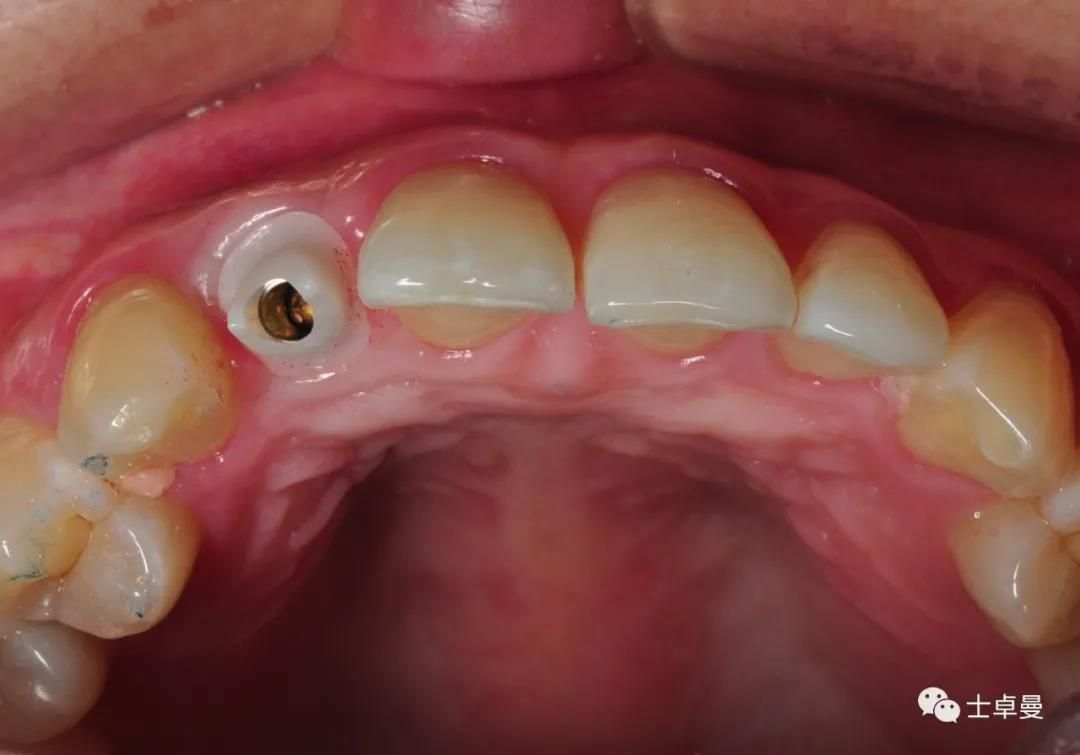

临时义齿口内就位

·        根尖片显示临时基台就位良好,无骨阻挡;

·        CBCT显示种植体三维位置良好;

术后 CBCT 显示种植体三维位置良好

·       10天后拆线,临时义齿稳定,牙龈愈合良好;